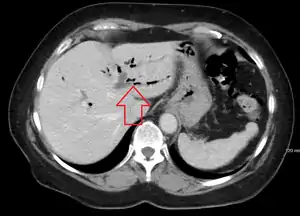

| CT scan of pneumobilia |